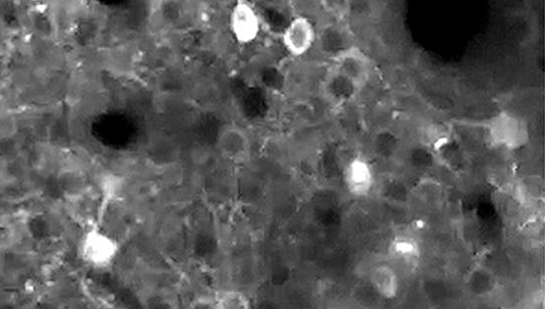

À 48 ans, je suis subitement frappé d’épilepsie. Elle est due à un dysfonctionnement soudain de mon hippocampe, organe cérébral qui façonne nos souvenirs à partir de sons, d’images, de récits qui s’enchevêtrent.